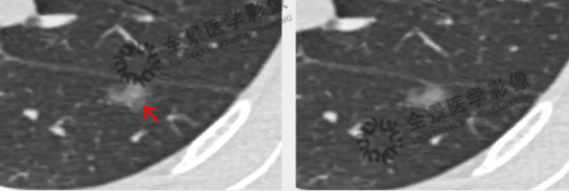

肺结节CT轴状面影像示例

肺结节CT轴状面影像示例(圈红处)